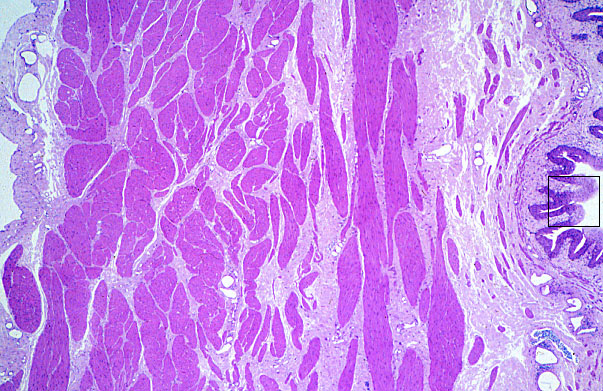

urinary bladder, relaxed

165. Urinary System urinary bladder, relaxed